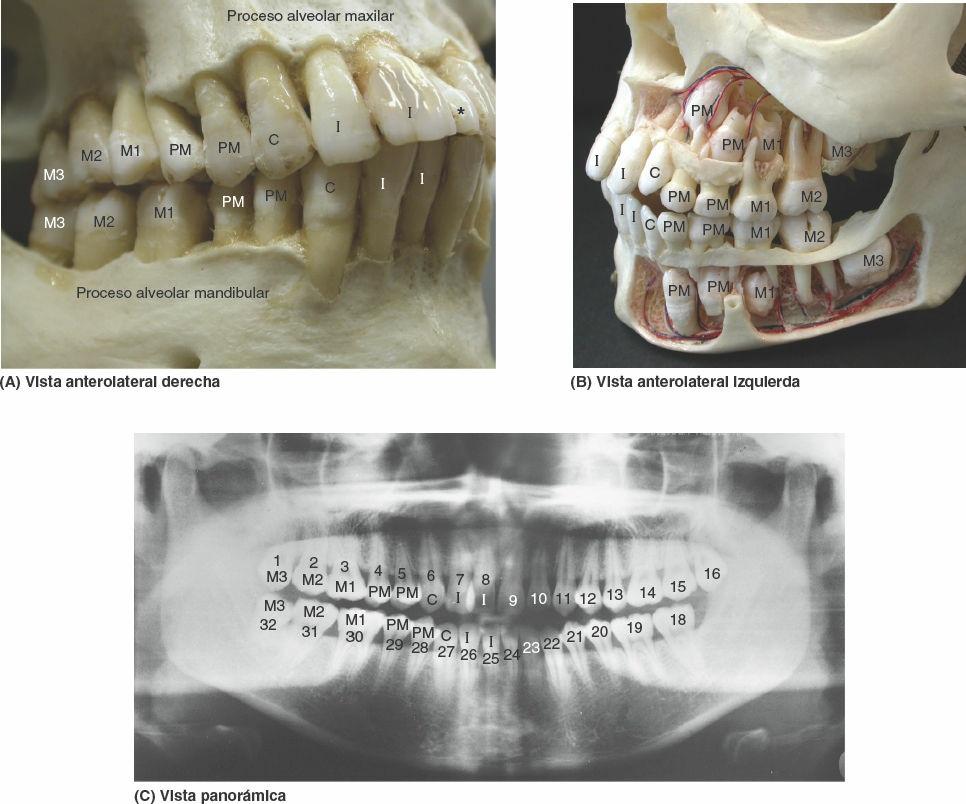

Los niños tienen 20 dientes deciduos; los adultos normalmente tienen 32 dientes permanentes (fig. 8-80 A y C). Las edades habituales de erupción de los dientes se exponen en la figura 8-81 y en las tablas 8-13 A y 8-13 B. Antes de la erupción, los dientes en desarrollo se alojan en los arcos alveolares en forma de gérmenes dentales (fig. 8-80 B).

Los tipos de dientes se distinguen por sus características: incisivos, de bordes delgados y cortantes; caninos, formados por un cono prominente; premolares (bicúspides) con dos cúspides; y molares, con tres o más cúspides (fig. 8-80 A y C).

Los dientes se componen de corona, cuello y raíz (fig. 8-82). La corona sobresale de la encía. El cuello se halla entre la corona y la raíz. La raíz está unida al alvéolo dentario por el periodonto (tejido conectivo rodeado de raíces); el número de raíces es variable. La mayor parte del diente está constituida por la dentina, cubierta por el esmalte sobre la corona, y por el cemento sobre la raíz. La cavidad pulpar contiene tejido conectivo, vasos sanguíneos y nervios. El conducto radicular (conducto pulpar) da paso a los nervios y vasos que entran y salen de la cavidad pulpar a través del foramen apical.

Los alvéolos dentarios (figs. 8-81 B y 8-82 B) se hallan en los procesos alveolares del maxilar y la parte alveolar de la mandíbula (fig. 8-80 A). Son las estructuras esqueléticas que experimentan un mayor cambio a lo largo de la vida (fig. 8-81 B). Los alvéolos adyacentes están separados por los septos interalveolares; dentro del alvéolo, las raíces de los dientes que poseen más de una raíz están separadas por los septos interradiculares (figs. 8-81 B y 8-82 B). El hueso del alvéolo posee una fina corteza que está separada de las cortezas labial y lingual adyacentes por una cantidad variable de hueso trabecular. La pared labial del alvéolo es particularmente delgada en los dientes incisivos; en cambio, en los molares, la pared más delgada es la lingual. Por lo tanto, habitualmente se rompe la cara labial para extraer los incisivos, y la cara lingual para extraer los molares.